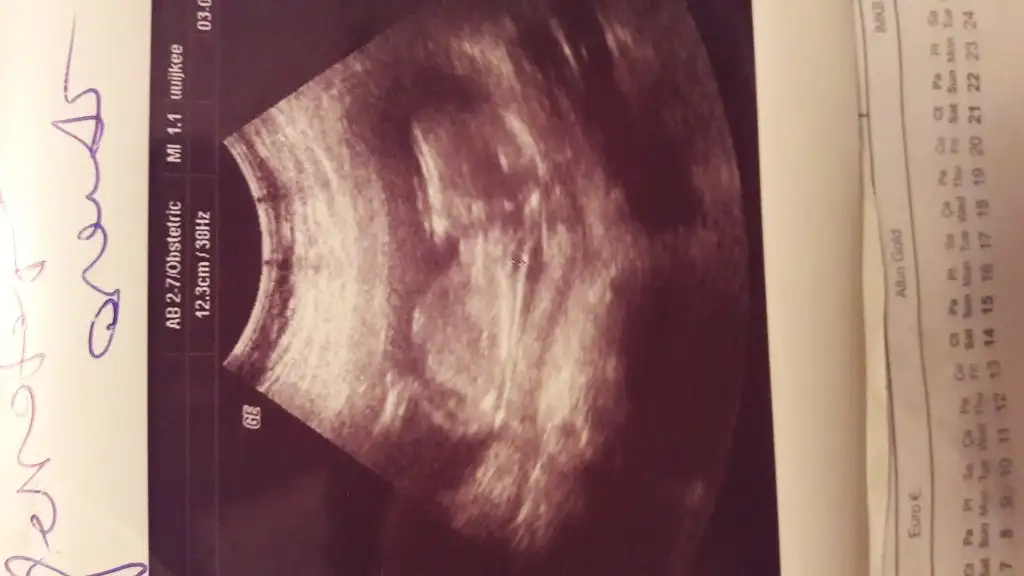

20200203_163234.webp

Gecen 12 haftalik istemistiniz bugun cekildik yine :) tahminde bulunabilir misiniz